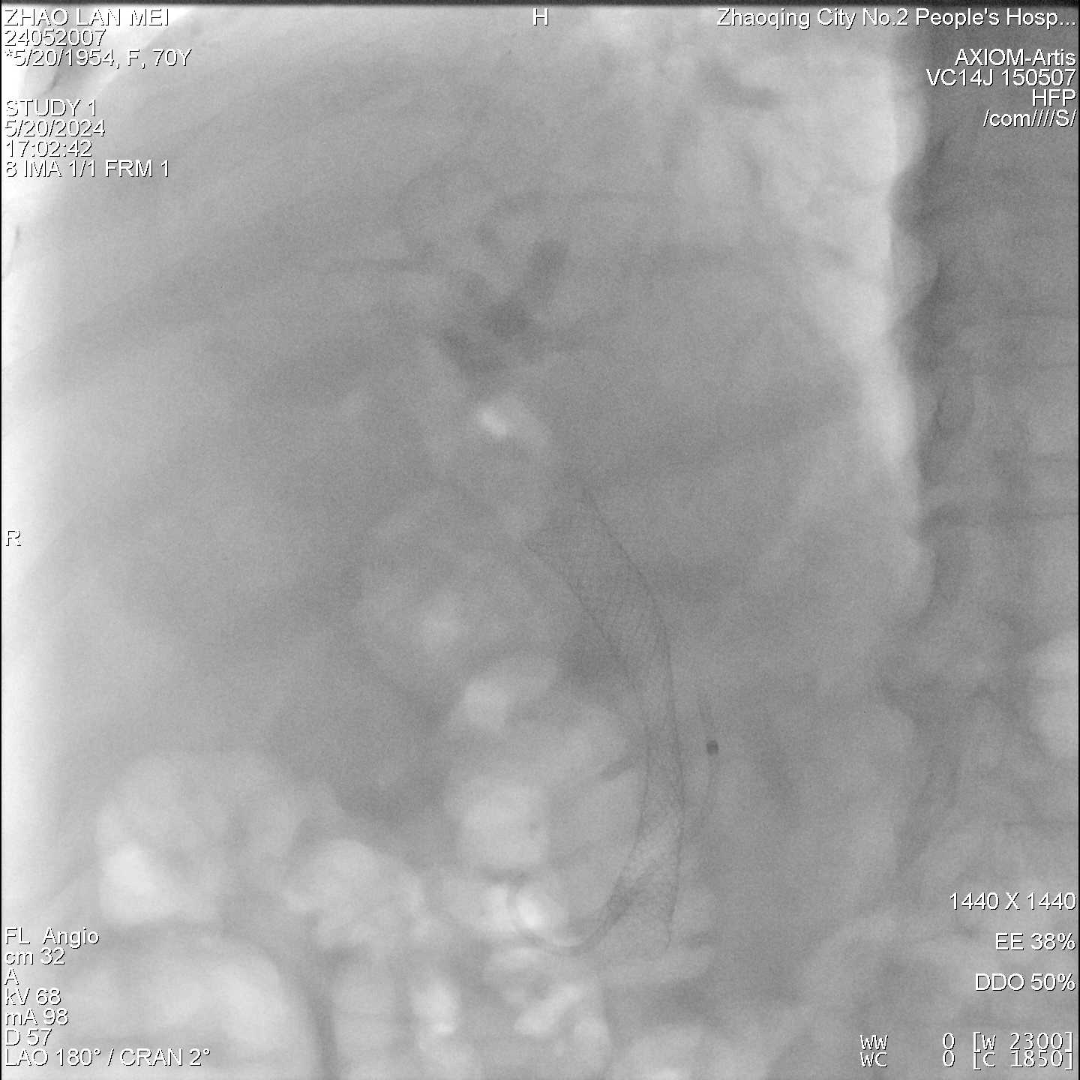

术前增强CT提示:胆总管下段占位?胆总管上段及肝内外胆管扩张